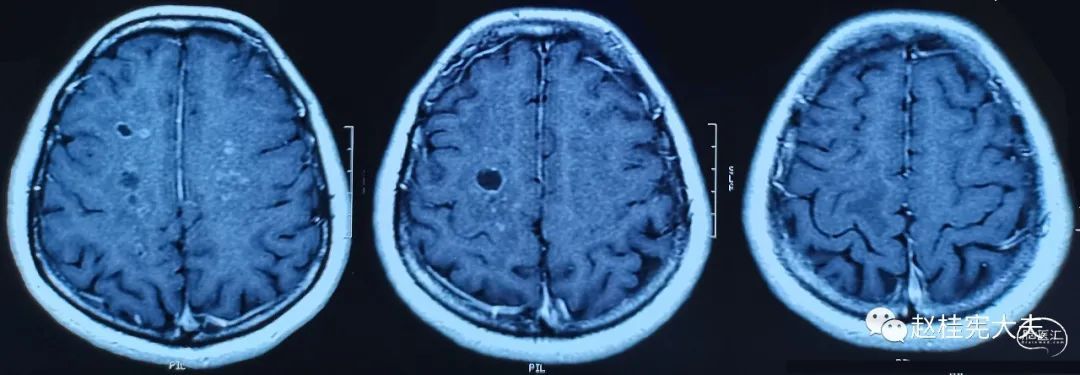

专病门诊时间,家属带患者来就诊。病史很简单,女性患者,56岁,以“反复头痛8年,加重2月”就诊。患者于8年前因头痛查颅脑CT提示颅内多发低密度影,行颅脑磁共振平扫+增强提示颅内多发病变,多个小囊,脑白质病变,病灶部分不规则强化,当地医院以寄生虫病服用打虫药3个疗程,症状同前,复查颅脑磁共振病灶未见明显变化。后未进一步诊治。2021年9月,因头痛加重,再次复查头颅磁共振平扫+增强提示颅内多发较大囊肿,弥漫性脑白质病变,再次查寄生虫抗体均阴性。目前诊断不明。